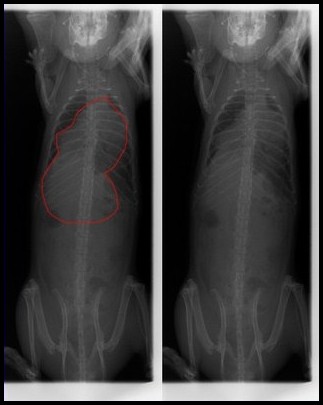

Il n'y a pas grand chose à faire, si ce n'est surveiller vos rats et agir au moindre doute. Des radios des poumons peuvent être effectuées en contrôle, les abcès y apparaissent comme des masses noires et trahissent la présence et l'activation de la maladie.

Ces photos peuvent être transmises à votre vétérinaire, afin de l'aider dans son diagnostic. Un abcès dans les poumons n'est pas toujours synonyme de corynébactéries actives, mais il convient de conserver ce détail en mémoire pour recouper les informations par la suite.

Poumons ayant des lésions typiques dues aux corynébactéries

Radio de cette rate, où on peut voir la masse